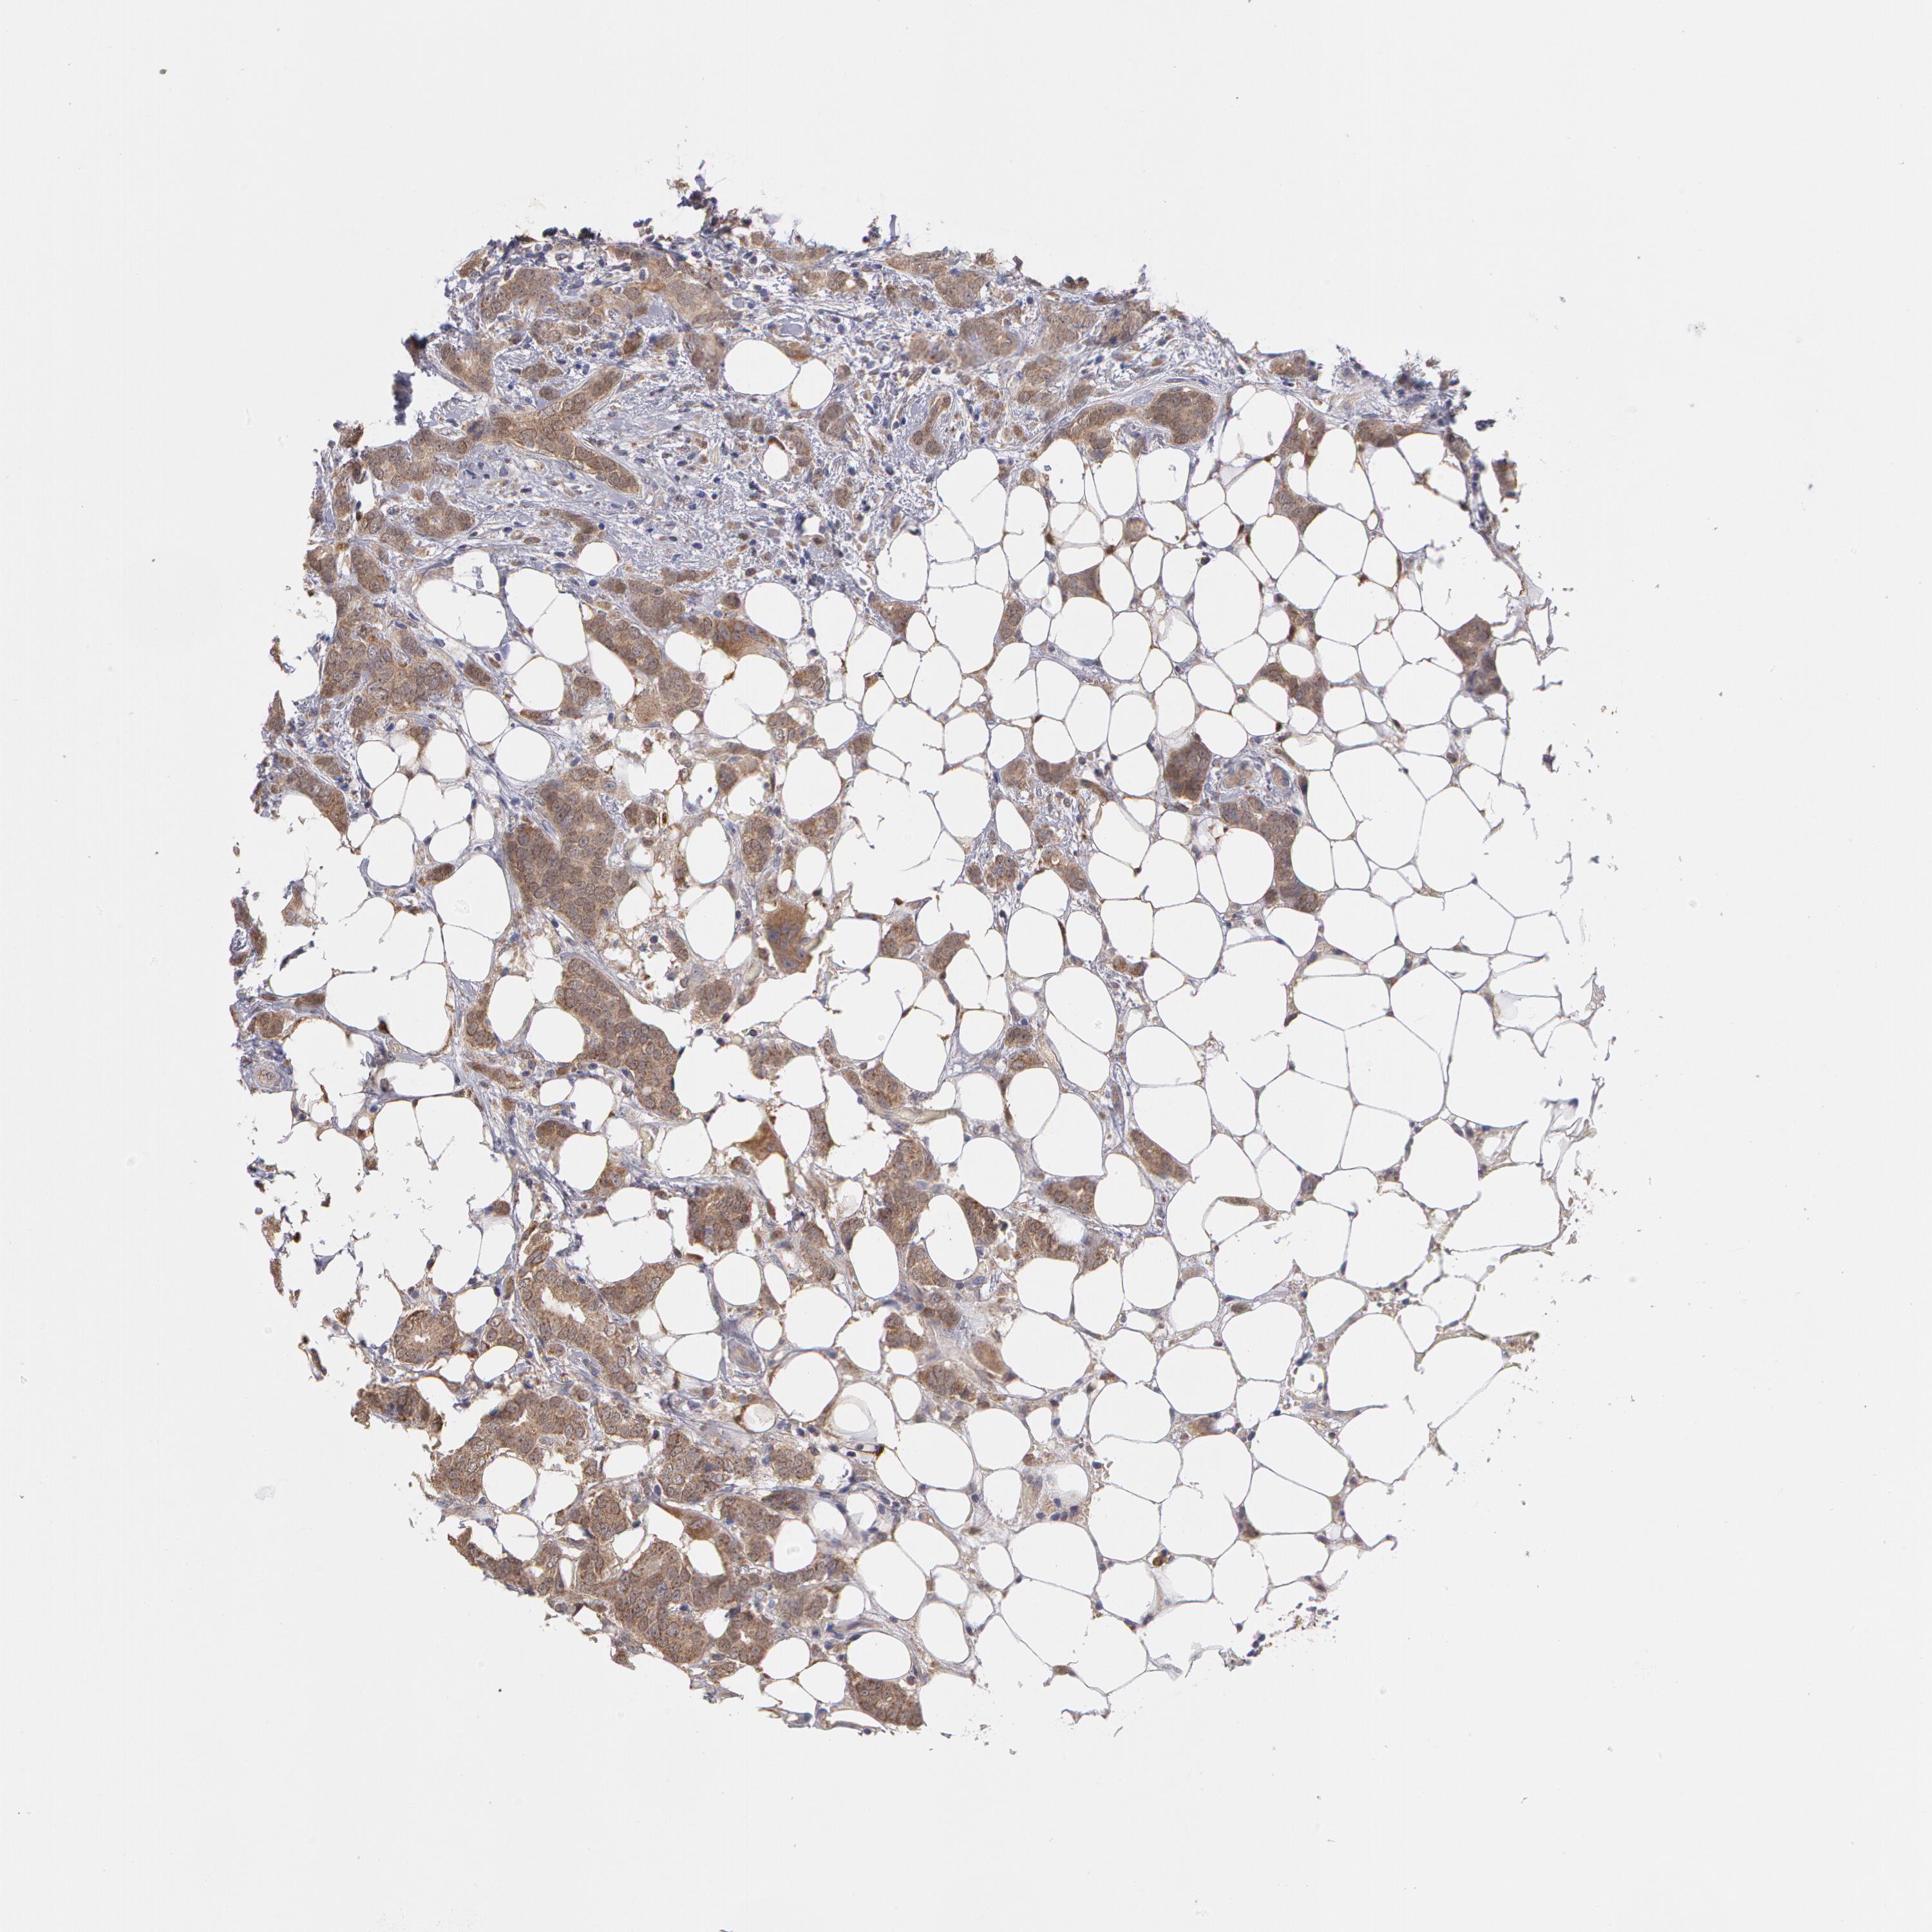

BRCA TCGA BRCA VALIDATION PROTEIN EXPRESSION